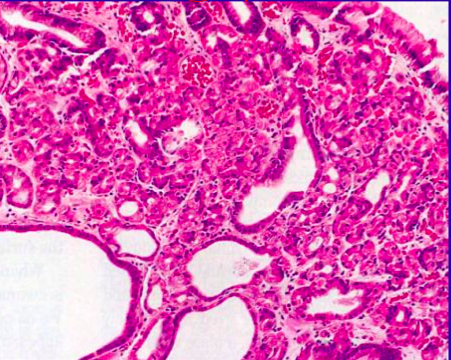

<p>Describe what is going on in this bx from a gastric wall mass.</p>

<p>These are normal pancreatic cells growing in the wall of the stomach.</p>

<ul>

<li>benign proliferation of cells from a pancreatic rest left by the budding of the pancreas from primordial gut tube.</li>

<li>most common congenital deformity of stomach to present in adults.</li>

<li>It can be dx'd just by gross appearance (seen here)</li>

</ul>